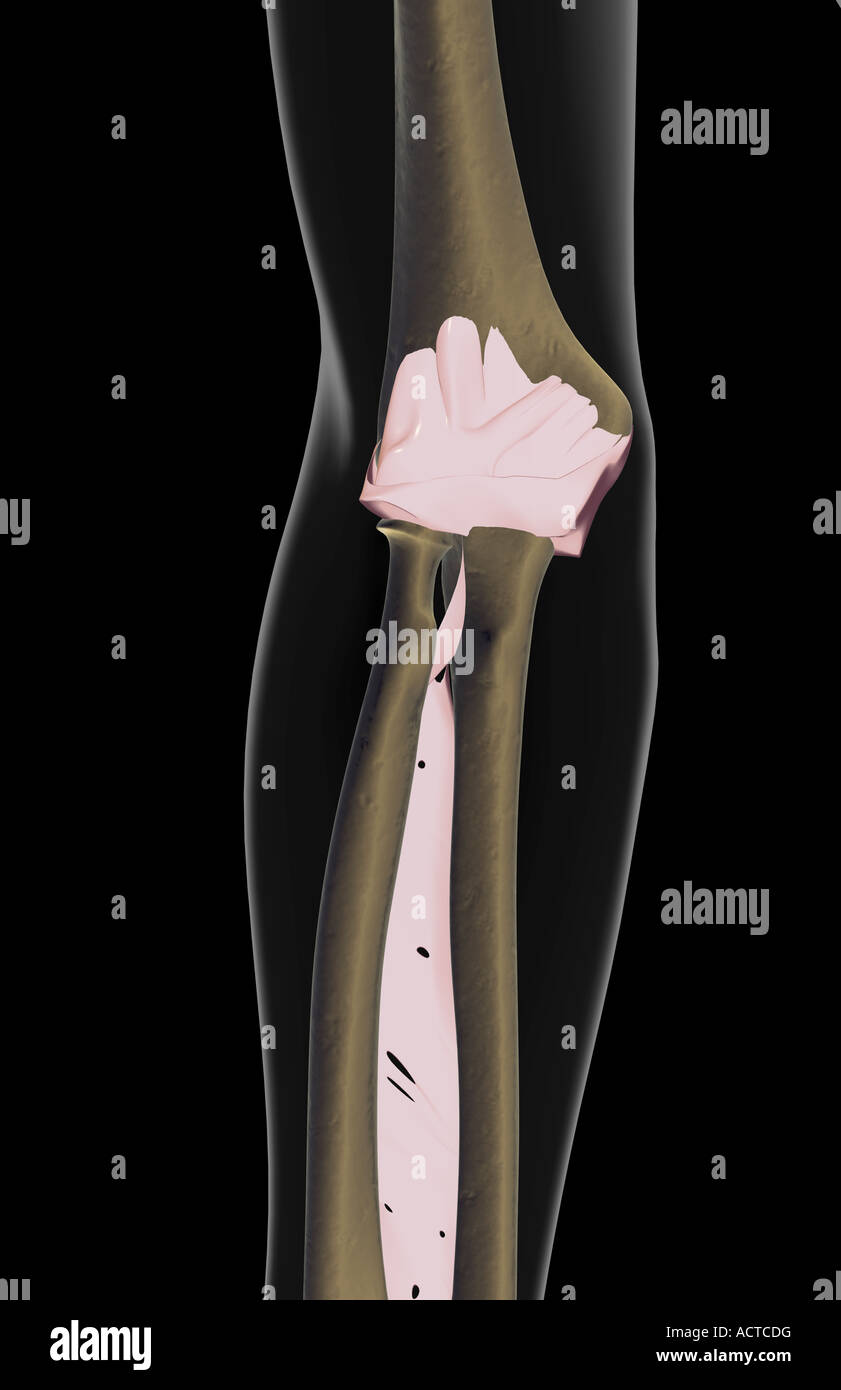

The ligaments of the elbow Stock Photohttps://www.alamy.com/image-license-details/?v=1https://www.alamy.com/stock-photo-the-ligaments-of-the-elbow-13225563.html

The ligaments of the elbow Stock Photohttps://www.alamy.com/image-license-details/?v=1https://www.alamy.com/stock-photo-the-ligaments-of-the-elbow-13225563.htmlRFACTCDG–The ligaments of the elbow

Ligaments of the elbow joint Stock Photohttps://www.alamy.com/image-license-details/?v=1https://www.alamy.com/stock-photo-ligaments-of-the-elbow-joint-13227958.html

Ligaments of the elbow joint Stock Photohttps://www.alamy.com/image-license-details/?v=1https://www.alamy.com/stock-photo-ligaments-of-the-elbow-joint-13227958.htmlRFACTKGR–Ligaments of the elbow joint